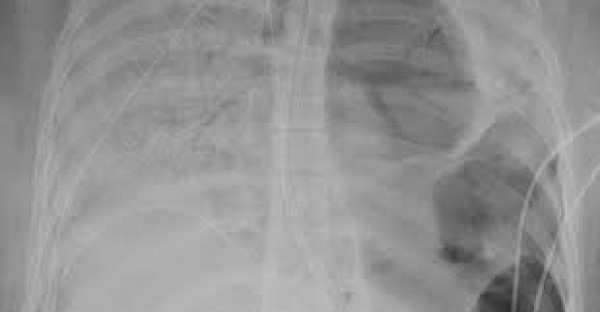

أكد البروفيسور "ماورو جياكا" من كلية "كينجز كوليدج" في لندن إن فيروس كورونا المستجد يترك بعض المرضى يعانون من رئتين متضررتين بشدة، حتى تصل لعدم قدرة الخبراء بالطب على تمييزها على أنها عضو.

وأضاف إن الفيروس يسبب اضطرابًا كاملًا في بنية الرئة ويمكن أن يسبب تجلط الدم أي تكوين جلطات دموية، بحسب ما نشرت (صدى البلد) عن صحيفة "ديلي ميرور" البريطانية.

وأشار :" في بعض الأضواء لا يمكنك حتى أن تميز أن هذا العضو هو رئة"، وفي حديثه عن إمكانية حدوث موجة ثانية، قال الأستاذ "جياكا" إنه سوف يحدث ارتفاعًا آخر في أعداد الإصابة بفيروس كورونا في مختلف الدول.

في الشهر الماضي ، نشرت صور لرئتي امرأة سليمة، ولكن في الصورة بعد الإصابة بالفيروس المستجد اتضح تدمير رئتيها، وقامت المريضة، التي كانت في العشرينات من عمرها، بإزالة العضو الحيوي في عملية زرع رئة مزدوجة نادرة بعد أن أصيبت بمرض مهدّد للحياة بسبب فيروس كوفيد -19 .

ووفقًا للمستشفى تعتبر هذه أول عملية زرع مزدوجة من نوعها في الولايات المتحدة حيث تواصل الدولة محاربة الوباء، وقد نشر الجراحون تفاصيل الحالة من أجل إظهار الأطباء الآخرين في جميع أنحاء العالم أن عمليات زرع الرئة يمكن أن تكون خيارًا قابلًا للتطبيق لبعض مرضى فيروس كورونا المصابين بأعراض شديدة.

وكانت الشابة من أصل اسباني قد نجت من العملية، وقال المستشفى إنها أمضت ستة أسابيع على جهاز دعم الحياة في العناية المركزة عندما أصبح هناك حاجة إلى تدخل جذري واضح.